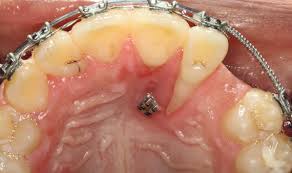

Röntgen beim zahnarzt wie oft im jahr. Dabei unterstützen uns auch zahlreiche Technologien wie beispielsweise das elektronische Längenmessgerät das uns während der Wurzelkanalbehandlung mitteilt wo der Wurzelkanal endet ohne dass hierfür eine Röntgenaufnahme notwendig wird. Die Anwendung von Röntgen erfolgt nach dem strengen Grundsatz. Das gilt etwa bei erhöhtem Kariesrisiko oder wurzelbehandelten Zähnen Zahnärzte müssen jedes Mal über die Notwendigkeit des Röntgens aufklären.

So wenig wie möglich so viel wie nötig. Mein Sohn 10 J ist in kieferorth. H äufiges Röntgen der Zähne erhöht das Risiko für einen gutartigen Hirntumor.

Wir versuchen die Röntgenaufnahmen dabei auf ein Minimum zu beschränken getreu dem Motto so wenig wie möglich so viel wie nötig. Sie muss zehn Jahre lang aufbewahrt werden. Das Zahnrönt-gen stellt somit ein wenig belastendes Diagnoseverfahren dar das im Verhältnis zur. Hallo ich möchte gern wisenwie oft ein 10 jähriger den Röntgenstrahlen in einem Jahr und allgemein ausgesetzt werden sollte ohnedass es für ihn gefährlich ist. So wenig wie möglich so viel wie nötig. 2x ist sicher besser aber die Entscheidung wie oft man das macht lasse ich mir nicht vom Zahnarzt. Die gesamte Mundsituation Frage vom. Mein Sohn 10 J ist in kieferorth. Ein Bekannter erzählte mir heute dass er bei seinen letzten drei Zahnarztbesuchen die allerdings auch schon vier Jahre auseinander lagen jeweils geröntgt worden sei.